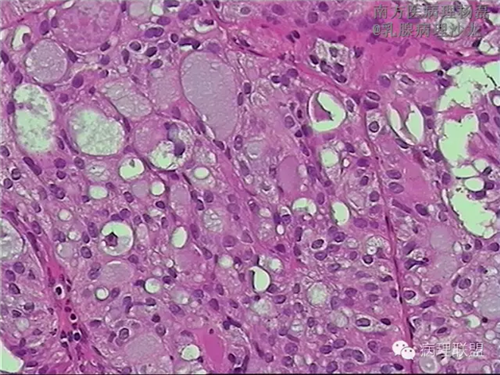

肺转移性乳腺分泌性癌?-病例讨论

女,51,右肺多发结节穿刺。15年前行右乳肿物切除,具体不详。